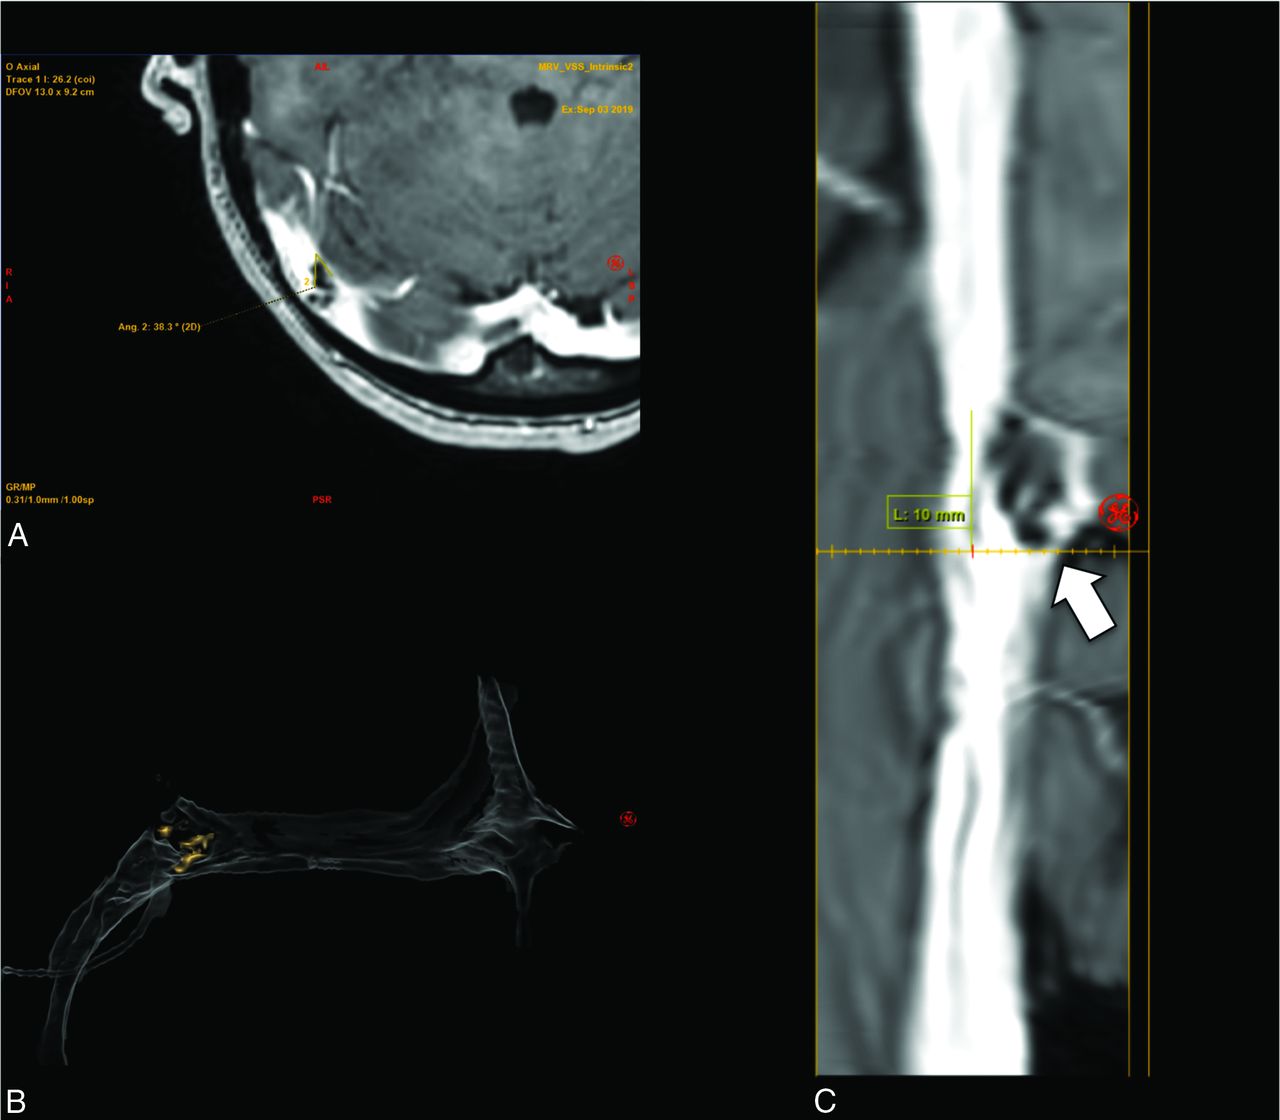

Straight-vessel views and 3D reconstructions of both TOF and contrast-enhanced images were created and reviewed to better characterize venous sinus anatomy and stenosis, as shown in Fig 2. The straightened vessel view was achieved using 2-click automatic vessel analysis (Vessel ASSIST; GE Healthcare). After the user selected the start and end points in the sigmoid sinus and superior sagittal sinus, the software automatically tracked the vessel and computed its centerline. The resulting vessel segmentation could be displayed as a 3D volume-rendered model or a lumen view (D). The lumen view is obtained by transforming the 3D vessel centerline into a straight line and displaying the corresponding perpendicular plane for each point on the line. For each position, minimum, mean, and maximum diameters were automatically computed.

A, 2-Click automatic vessel analysis start point selection in the sigmoid sinus (short arrow). B, 2-Click automatic vessel analysis end point selection (short arrow) in the superior sagittal sinus (long arrow). C, 3D volume-rendered vessel segmentation. D, Lumen view shows the straightened vessel segmentation.